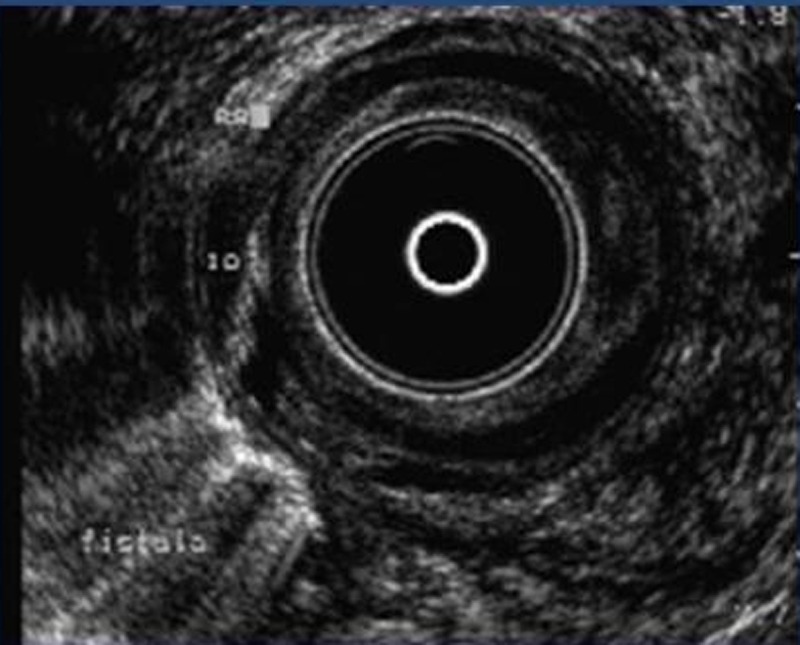

Rectoanal ultrasonography represents a significant advancement in the diagnostic approach and investigation of lesion extent within the anorectal canal. This … More